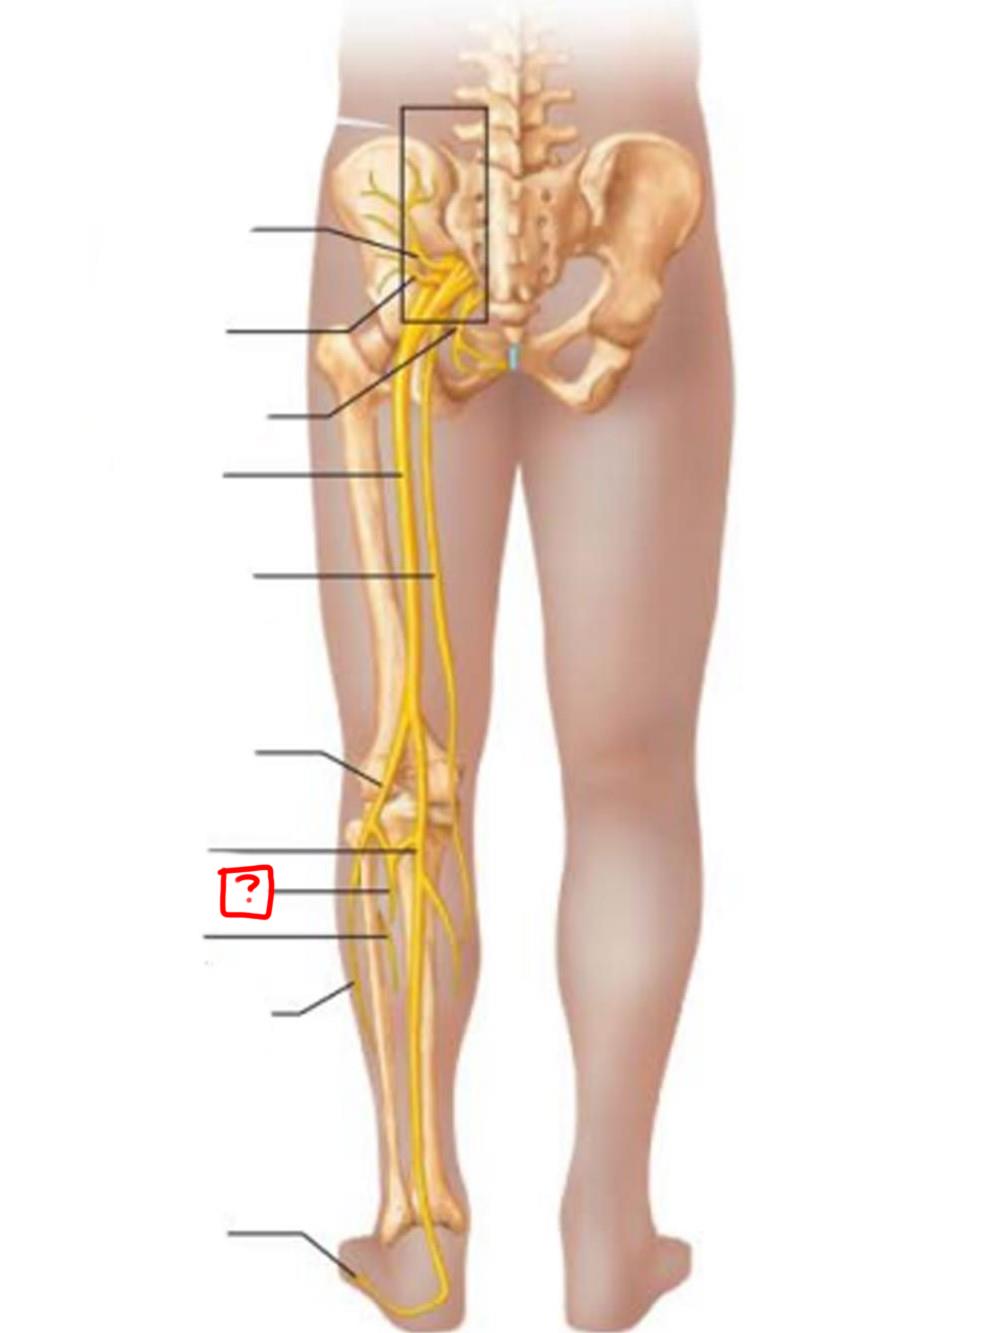

sciatic

posterior femoral cutaneous

common fibular

tibial nerve

sural (cut)

deep fibular

superficial fibular

plantar branches